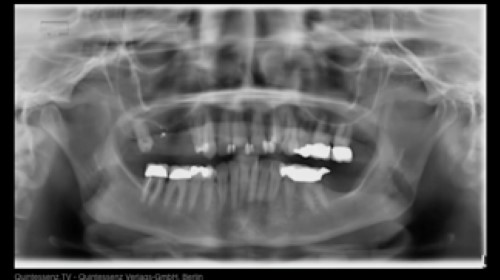

For the prosthetic restoration of single toaoth implants, a variety of treatment options exists: Metal or ceramic abutments, screw-retained or cemented crowns, all-ceramic or metal-ceramic crowns etc. This module will guide you through these treatment options and help you to take evidence-based decisions.

• Discuss the restorative treatment options for implant single crowns in esthetic and non-esthetic areas and their benefits and limitations

• Perform conditioning procedures of the peri-implant soft tissues in esthetic and non-esthetic areas

• Evaluate the esthetic impact of different abutment and crown materials

•  Decide which type is best suitable in esthetic and non-esthetic areas

• Understand the digital workflow in implant prosthodontics and evaluate the possibilities and limitations